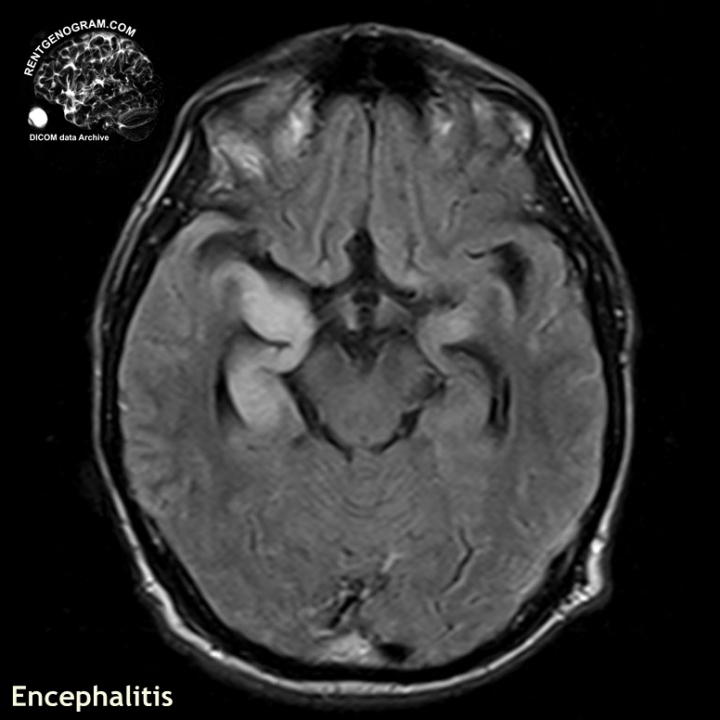

Иллюстрации и пояснения: гиподенсивный очаг на КТ головного мозга